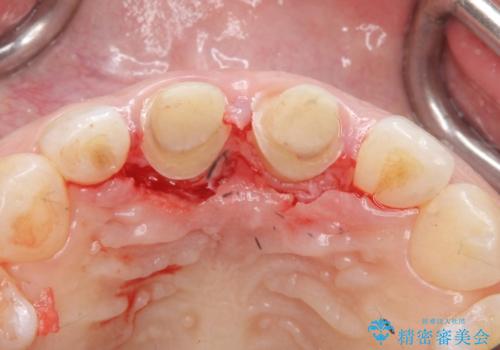

その後、マージンが舌側が深い状態だったため、歯ぐきの手術(歯周外科処置:APF)を行ってから最終的なセラミックを装着しました。

- 117万円(矯正治療:90万円 上顎両側 1 ジルコニアクラウン(スペシャル):13万円x2、仮歯:1万円x2 矯正用高強度仮歯:2万円x2 歯周外科手術(APF):5万円)費用は治療当時の料金となります